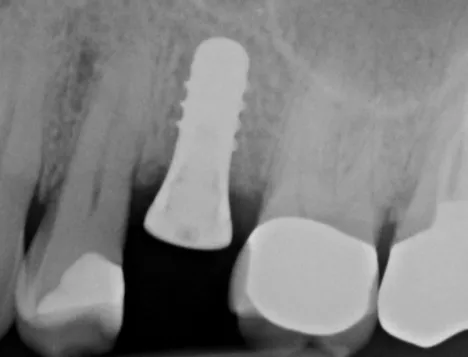

Dr.-Geivelis_Fig.6

Fig. 6. X-ray image of implant immediately after placement, 5.5 months after extraction and graft